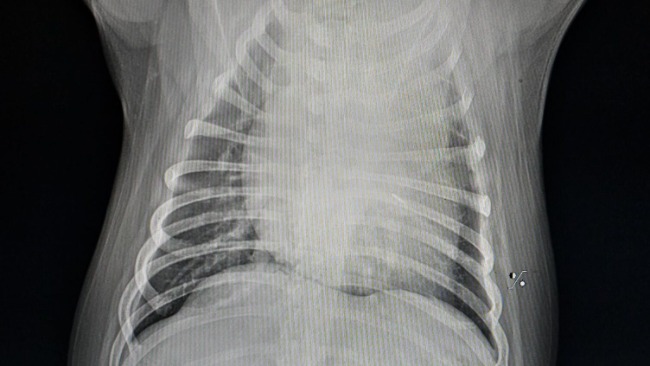

Od tego momentu zostało wykonane RTG, liczne USG, badania krwi, Echo serca...i w koncu TK z kontrastem, które niestety potwierdziło bardzo smutną dla mnie diagnozę...guz podstawy serca💔

Guz o średnicy 4,5 cm uciska mu aortę i tchawicę. Niestety są już także przerzuty w węzłach chłonnych śródpiersia.

Pomimo tak strasznej diagnozy, Keko jest w dobrej kondycji klinicznej, ma apetyt i uwielbia spacery, coprawda już w swoim własnym tempie, bo ma nadciśnienie płucne i zadyszkę, przez ucisk guza na tchawicę i płuca.